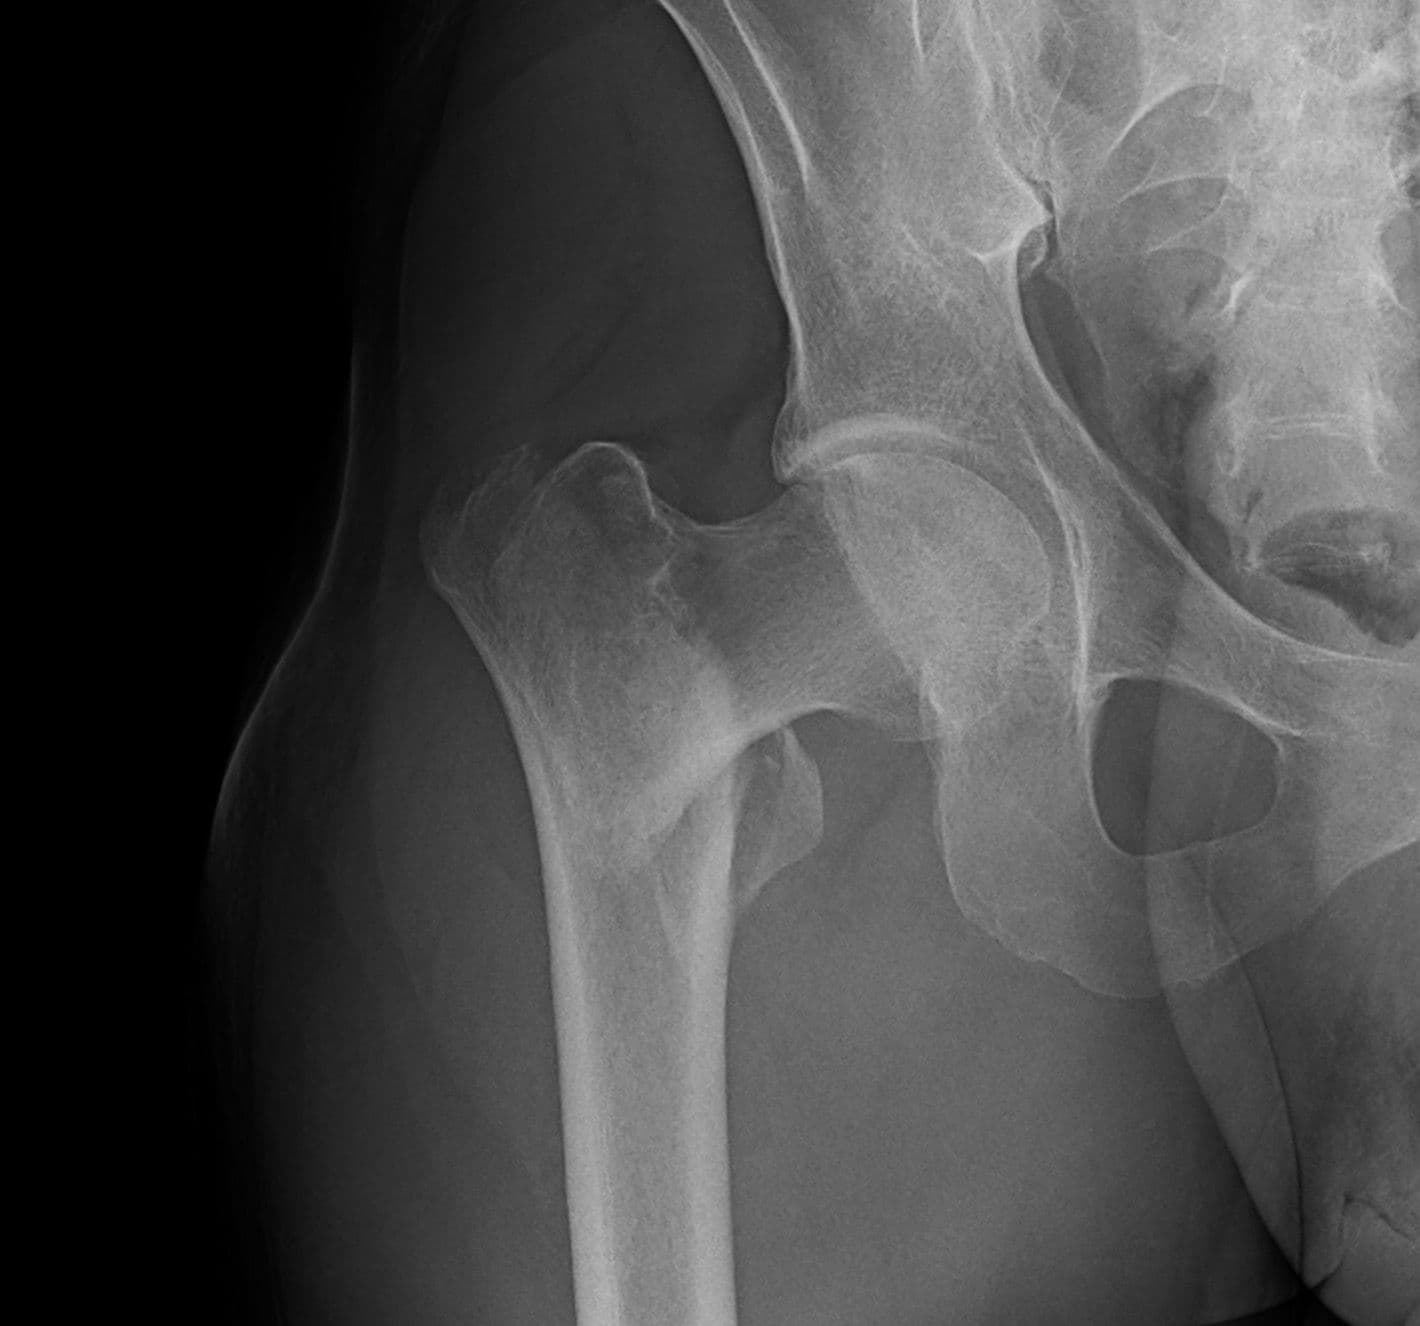

Intertrochanteric Fracture Short Nail